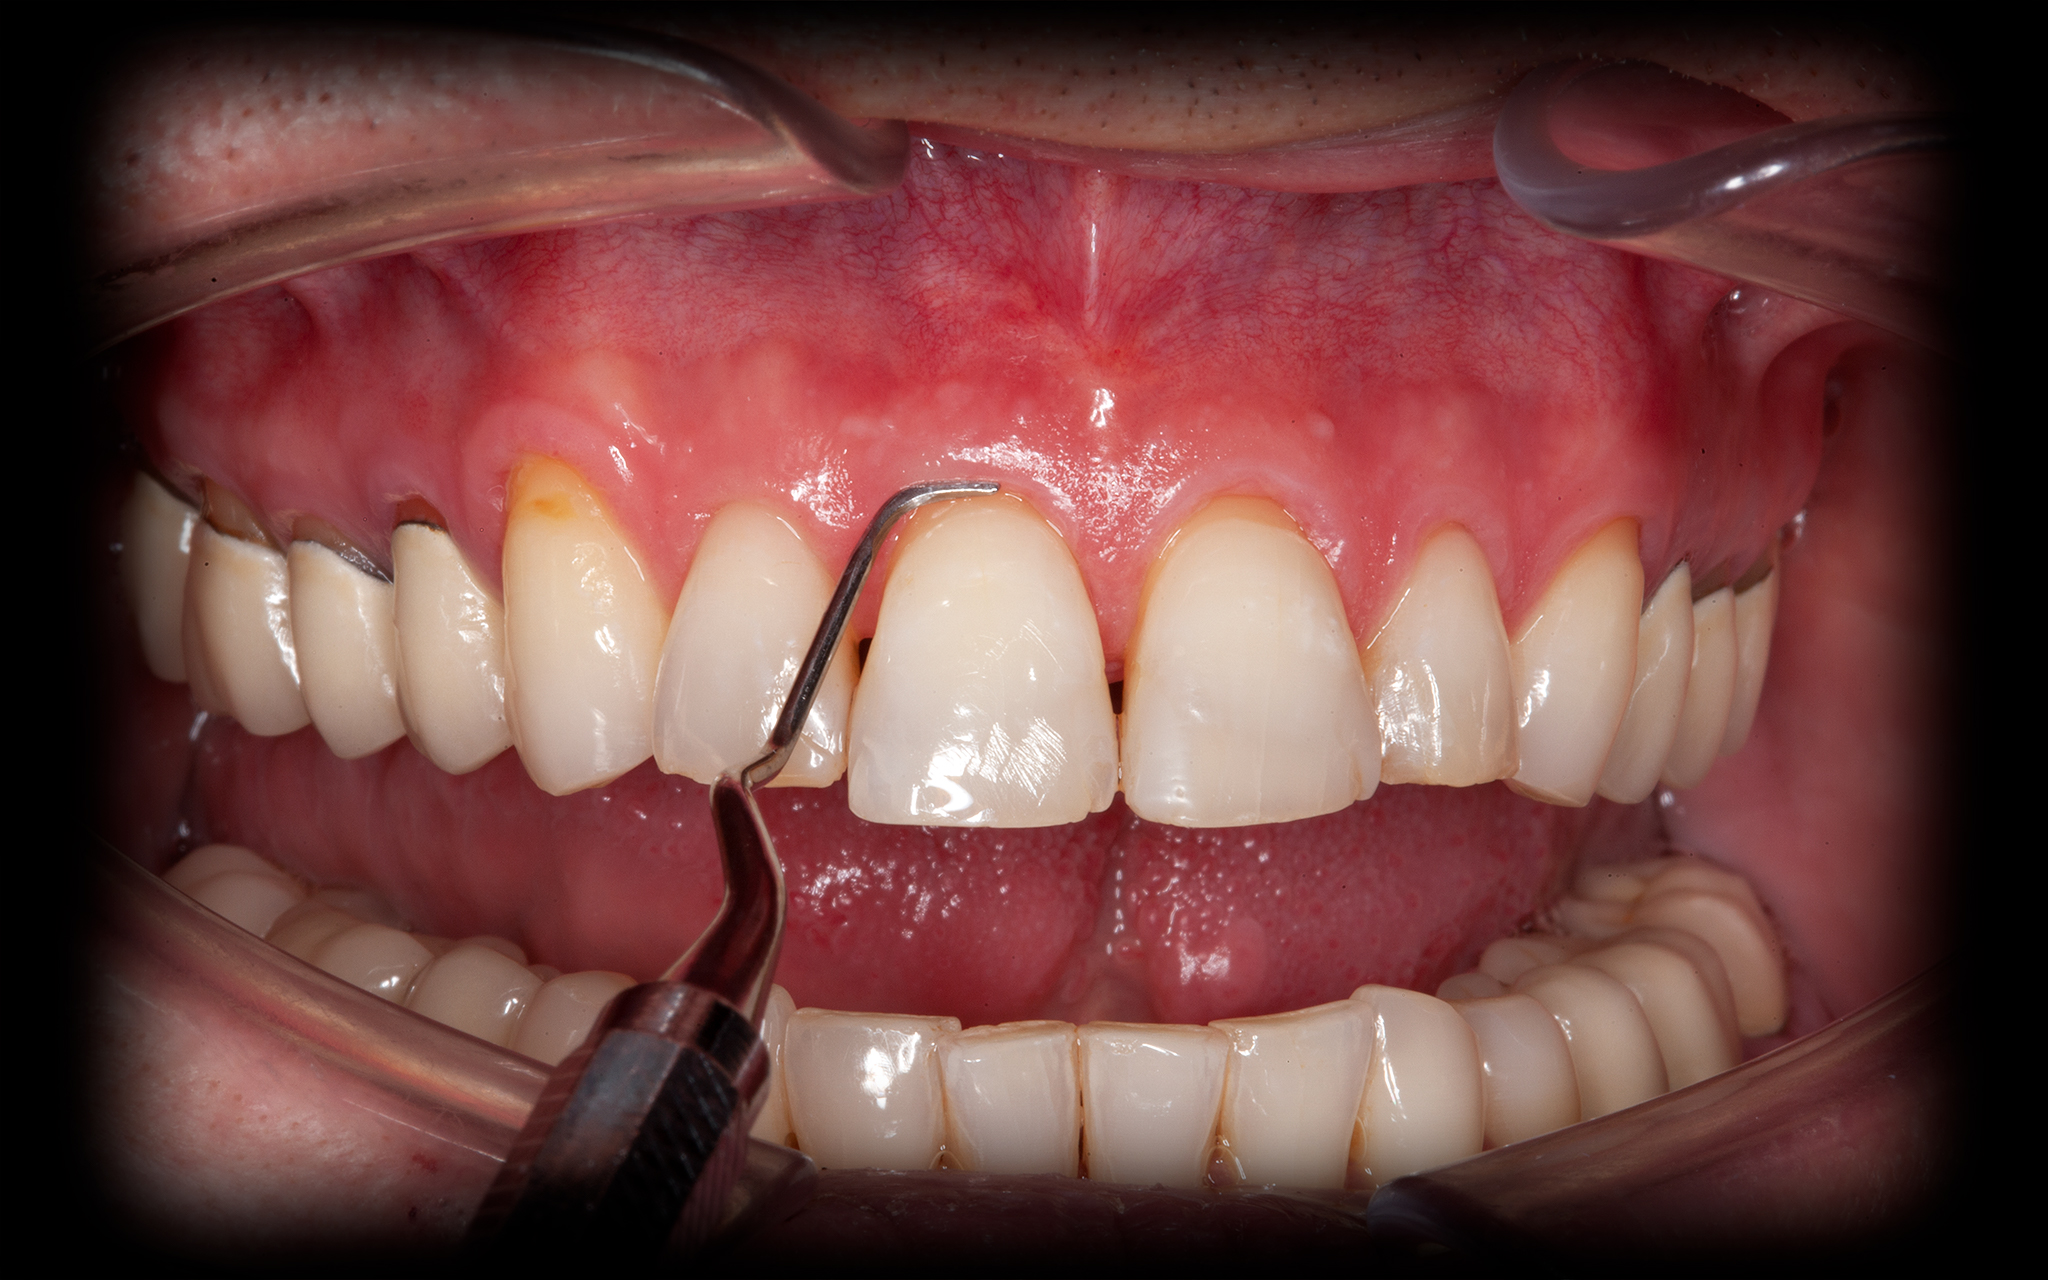

Ausgangssituation

Bei Behandlungsbeginn

• Freiliegende Zahnhälse

• Funktionell überbelastete Frontzähne

• Schmelzfrakturen an den Schneidekanten

Professionelle Mundhygiene und Entfernung des Biofilms über sowie unter dem Zahnfleisch (GBT)